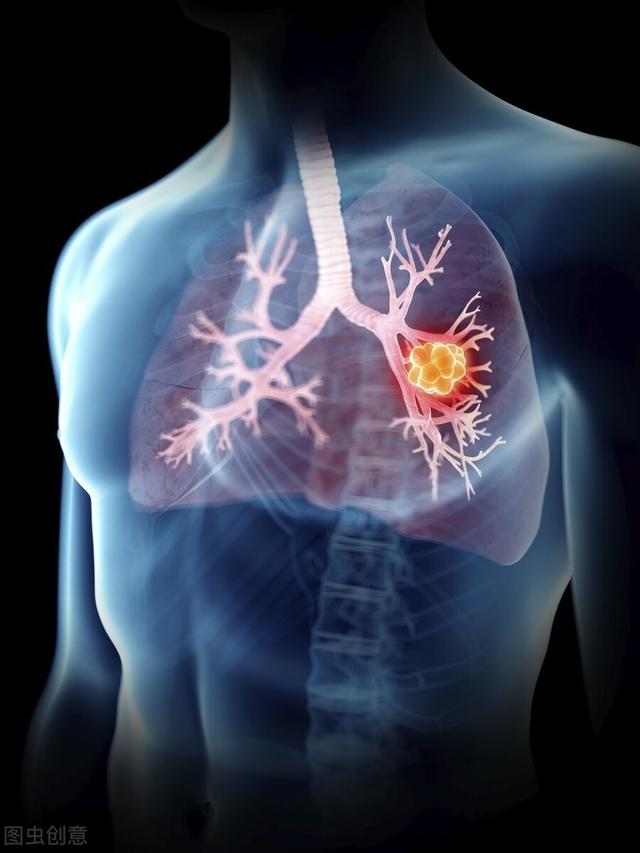

肺がんは現在、こう呼ばれている。ナンバーワン世界的にがん関連死で最も多い主要がんこの上なくその理由は。WHOが発表したデータによると、2012年だけでも、世界中で肺がんを発症した人の数は182.5万ドルこれは、全がん罹患者数と死亡者数の13.0%を占めている。1億5,900万ドル全がん死亡者の19.4%を占める!

これがいかに膨大な人口であるかは想像に難くない。したがって、肺がんの早期発見、早期診断、早期治療は非常に重要である。もちろん、肺がんが第1位というのは、罹患率も死亡率も第1位であることと密接な関係がありますが、同様に肺がんの症状が多く、非定型的なものが多いことも関係しています。では、肺がんが腰痛を引き起こす可能性はあるのでしょうか?もしそうだとしたら、肺がんによる腰痛と通常の腰痛の違いは何なのでしょうか?一般人である私たちは、それをどのように見分ければよいのでしょうか?今日はその話をしよう。

肺がんが背中の痛みを引き起こす可能性はあるのでしょうか?もしそうなら、何が原因なのでしょうか?

まずはその答えから:肺がんは背中の痛みを引き起こすことがある。.しかし、それは典型的なものではなく、一般的なものでもない。想像を絶する,つまらない結局のところ、私たちの肺がんは胸部で発生するのであって、これがどうして背中まで走るのか、ちょっと理解できない。

肺がんによる背中の痛みの原因は、大きく分けて2つある。ひとつは、肺がんの胸膜への浸潤によって引き起こされる、同じ脊髄分節の背部領域の引きつるような痛みである。もう1つは、肺癌の胸椎への転移による痛みである。

私たちは知っている。肺がんの初期段階では、明らかな症状は現れないしかし、がんの漸増に伴い、身体的な不快感、特に胸痛やその他の不快感、背部痛が現れ始めた。肺がんが悪化すると、隠れた痛み、背中の痛みや鈍痛が生じることがある。断続的なエピソードを味わう。この痛みや不快感の期間は非典型的なもので、緊張や五十肩などの病気が原因と考えられることが多い。

そして肺がんが悪化するにつれて胸膜に浸潤した後、痛みは咳や呼吸によって悪化する。例えば、咳をすると痛みが著しく悪化する。痛みの大部分は病変側にあり、健側には痛みがない。

そして肺がんがさらに悪化したとき。骨転移や肋骨転移があり、痛みが強い場合。これは、ドリルで穴をあけるような痛みと表現する人もいる。鎮痛剤で和らげなければならないこともある。

そのため、肺がんによる痛みは初期段階では目立たず、後期になってから徐々にその特徴が現れる。刺激性の空咳、喀血、嗜眠、食欲不振などの症状を伴うことが多い。